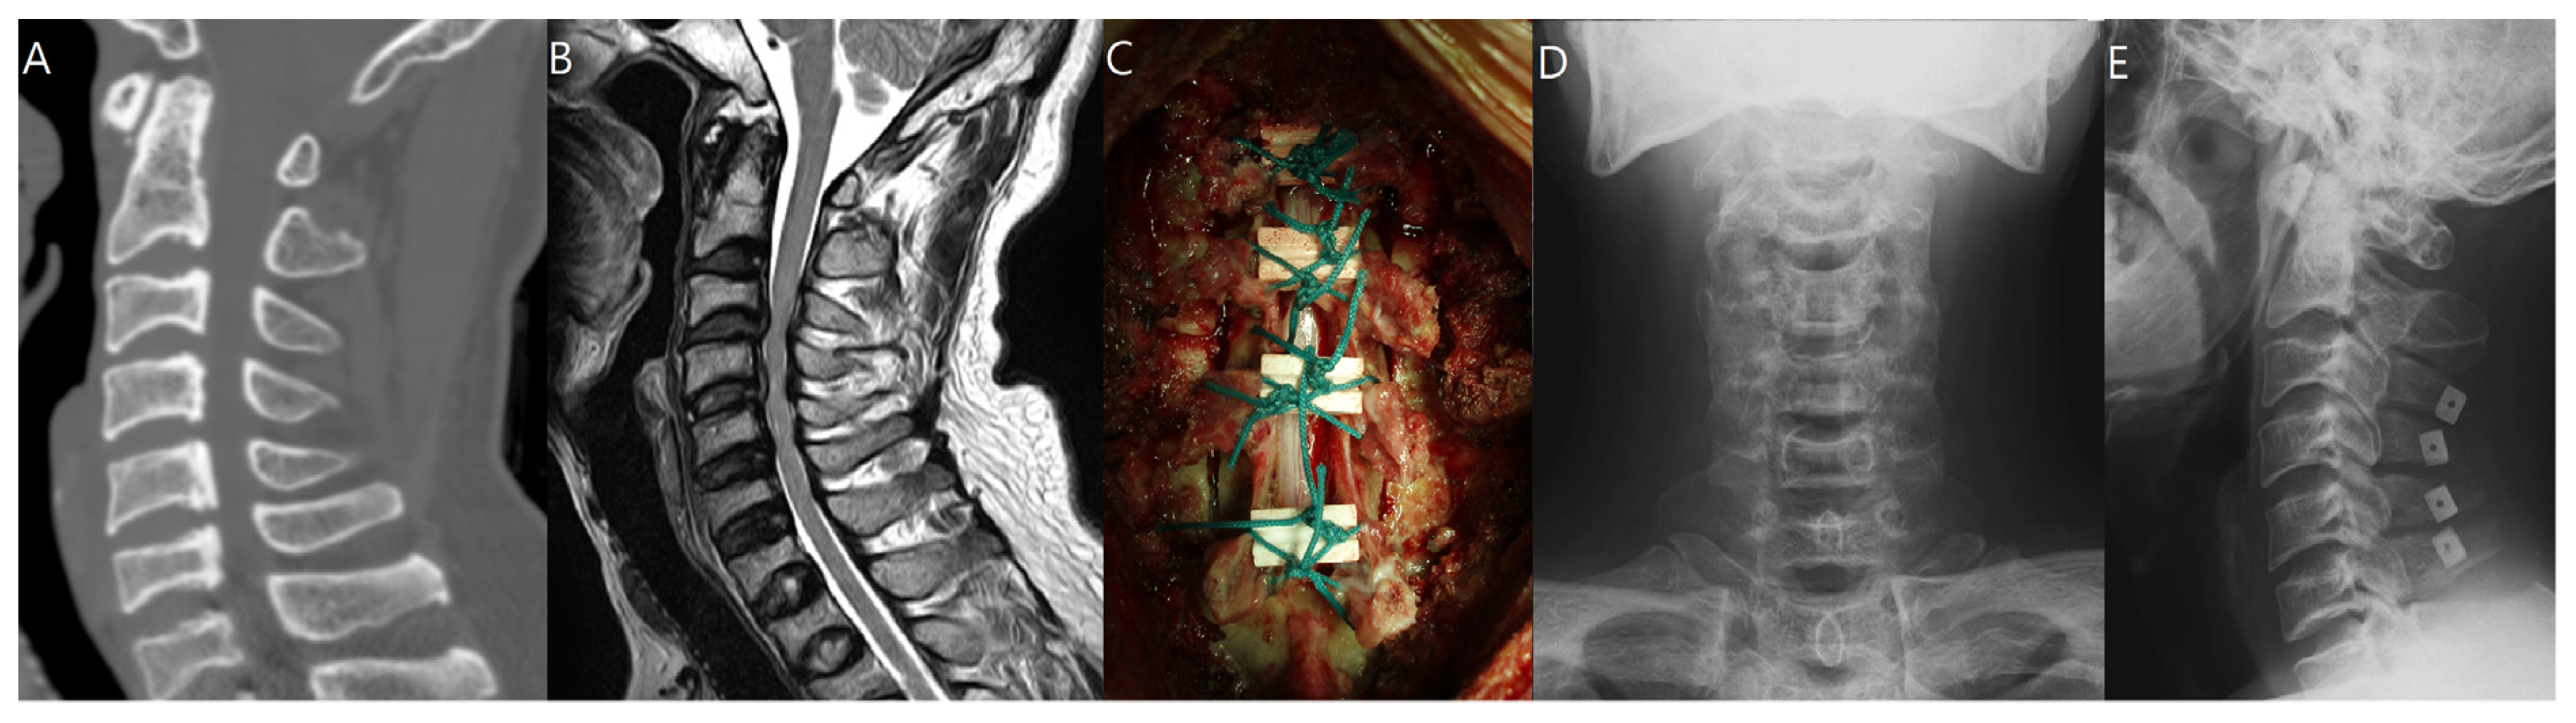

2.2. Surgical Technique